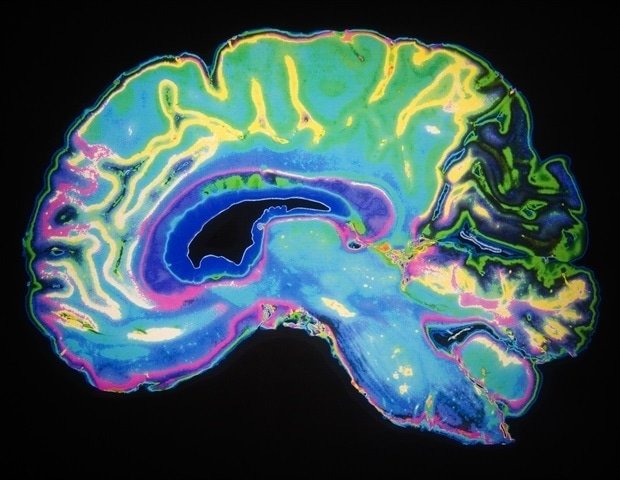

Posted online at Nature communicationsthe new work identifies for the first time the region of the brain called the high-level visual cortex (HLVC) as the place where “priors”—images seen in the past and then stored—are accessed to enable one-shot perceptual learning.

The researchers “took pictures” of brain activity during the previous access using functional magnetic resonance imaging (fMRI), which measures the activity of brain cells by monitoring blood flow to active cells. Signaling strength along neural pathways (plasticity), however, is fine-tuned at the structural spaces (synapses) between brain cells, and fMRI can only measure activity within cells.

The team then built statistical models that recorded patterns of brain cell activity via fMRI during prior access and found that only known patterns of neural coding in the high-level visual cortex matched the properties of the priors revealed by the behavioral study. The authors also investigated the temporal properties of activity changes using intracranial electroencephalography (iEEG) by asking patients already undergoing iEEG monitoring during neurosurgical treatment to perform a brief perceptual task. iEEG collects signals from electrodes in brain tissue to measure rapidly changing signaling patterns that fMRI cannot measure. HLVC showed the first changes in neural signaling strength, just as earlier guided object recognition did.